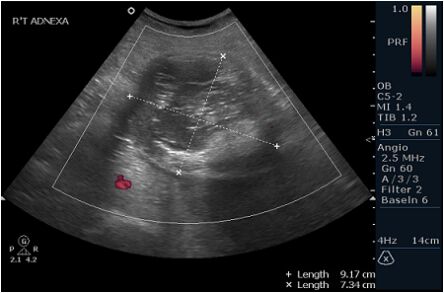

48.30歲女性,在健康檢查時,意外在骨盆超音波下,發現如圖所示之腫塊,最有可能的診斷為 何? (A)出血性黃體囊腫(hemorrhagic corpus luteum) (B)子宮內膜異位瘤(endometrioma) (C)畸胎瘤(teratoma) (D)功能性囊腫(functional cyst)